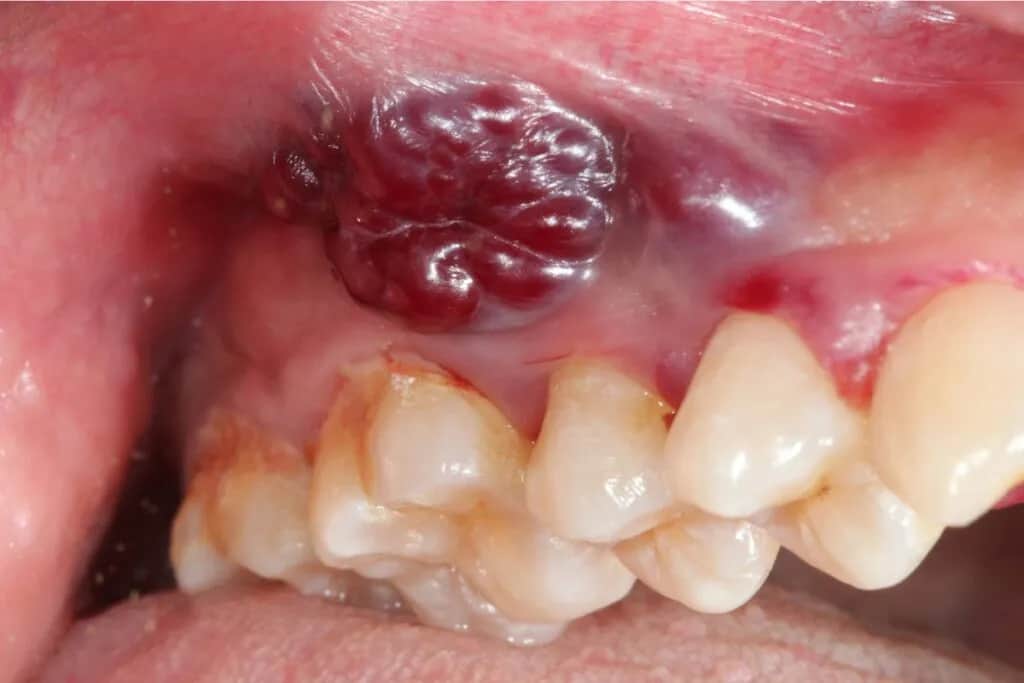

Widoczny guz "kalafiorowaty": charakterystyczny wygląd zaawansowanej zmiany

Jednym z najbardziej charakterystycznych objawów zaawansowanego raka jamy ustnej jest widoczny guz, często opisywany jako "kalafiorowaty". Jest to brodawkowaty lub kalafiorowaty rozrost tkanki, który łatwo krwawi przy dotyku. Taka zmiana jest już zazwyczaj duża i nie pozostawia wątpliwości co do konieczności natychmiastowej konsultacji.